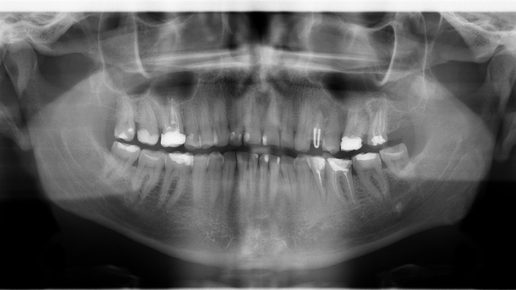

Сегодня поговорим о зубах. Хотя я врач и по идее должен знать о медицине больше чем люди других профессий, но всё таки я не стоматолог. Тем не менее мне хочется поделиться своим опытом в решении своих проблем. Так как мне почти 57 лет, то к этому возрасту я уже (увы) потерял несколько зубов. Новые зубы у людей пока ещё не вырастают (хотя, насколько я знаю работы в этом направлении ведутся). Но пока ещё самым распространённым и надёжным способом восстановления утраченных зубов является установка имплантов...